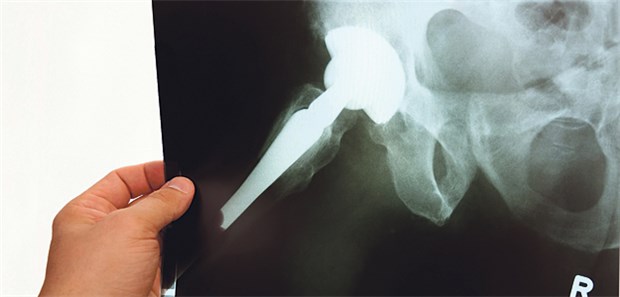

Künstliches Hüftgelenk im Röntgenbild: Bei ein bis drei Prozent der Endoprothesen treten Infektionen auf.

© the_builder / fotolia.com

Hüfte und Knie

Das Problem mit Infektionen am Gelenkersatz